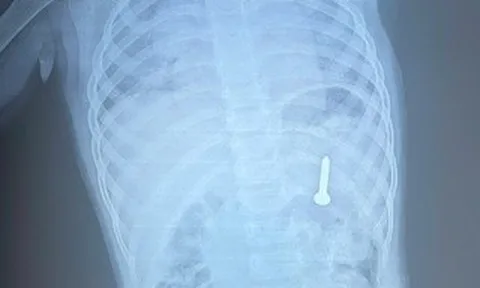

Người đàn ông đau bụng 36 tiếng, bác sĩ phát hiện "bí mật" bên trong

Các bác sĩ đã lấy ra chiếc chai nhựa mắc kẹt bên trong cơ thể một người đàn ông 38 tuổi sau một ca mổ phức tạp kéo dài hơn một giờ.